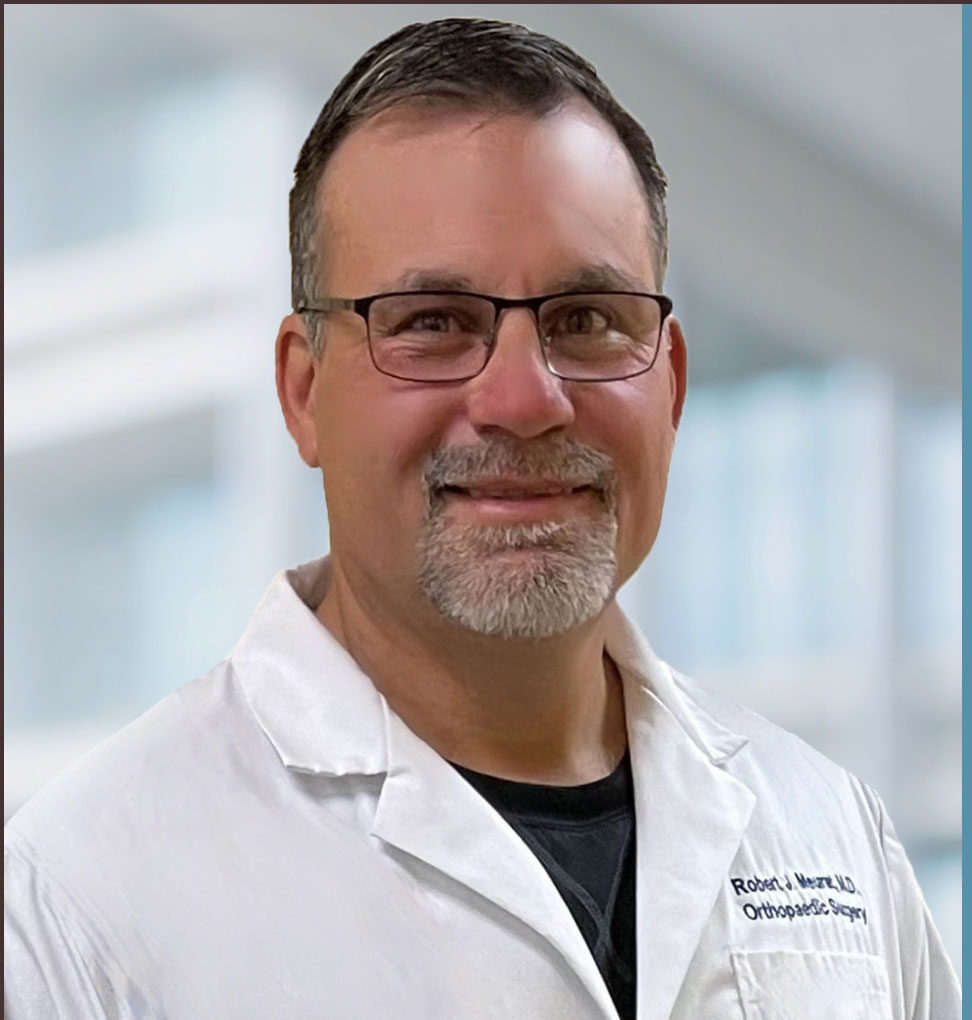

Board-Certified Orthopedic Surgeon Hip and Knee Replacement Specialist

Board-Certified Orthopedic Surgeon Fellowship-Trained in Trauma

Board-Certified Orthopedic Surgeon Subspecialty Trained and Board-Certified in Orthopaedic Sports Medicine